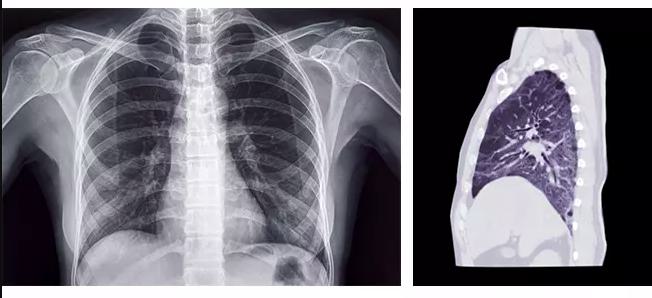

Medical imaging has transformed the way doctors detect, diagnose, and monitor cancer. Among the most commonly used imaging techniques is the CT scan with contrast, a test that provides detailed cross-sectional images of the body’s internal structures. For patients and families facing cancer concerns, one of the most common questions is: what does cancer look like on a CT scan with contrast?

A CT scan (computed tomography scan) is an imaging test that uses X-rays and computer technology to produce detailed images of organs, tissues, and bones. When contrast dye is used—administered orally, intravenously, or both—it helps highlight abnormal areas by making them appear brighter or darker than surrounding tissues. On a CT scan with contrast, cancerous lesions often show up as irregularly shaped masses, sometimes with different densities compared to healthy tissue.

Cancer may appear differently on CT scans depending on the type of tumor and its location.

• Solid tumors: Appear as dense, irregular masses that may invade nearby tissues.

• Cystic tumors: Contain fluid and may look like dark or hollow spaces.

• Metastatic cancer: Often appears as multiple small lesions scattered throughout an organ such as the liver or lungs.

• Calcified tumors: May show calcium deposits, which are seen as very bright spots.

A CT scan with contrast is often one of the first steps in diagnosing cancer. Radiologists look for signs such as unusual shapes, sizes, or textures of organs and tissues. Contrast dye highlights blood vessels and tumor blood supply, making malignant growths easier to detect. In most cases, CT results are combined with other diagnostic methods such as MRI, PET scans, blood tests, and biopsy to confirm whether a mass is cancerous.

So, what does cancer look like on a CT scan with contrast? Typically, it appears as irregular, dense, or unusual masses that stand out from surrounding healthy tissues when highlighted by contrast dye. While CT scans are a powerful tool, they are just one part of a comprehensive diagnostic process that includes biopsies and other tests. Early detection through imaging, combined with timely treatment and lifestyle changes, can significantly improve patient outcomes.